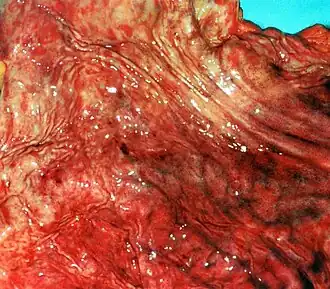

Gastritis erosiva | ||

- Gastritis erosiva. Se caracteriza por erosiones superficiales y múltiples en la mucosa del estómago, suele producirse por ingesta de antiinflamatorios no esteroideos y puede provocar la aparición de hemorragia digestiva. En algunos casos puede evolucionar a úlcera péptica.